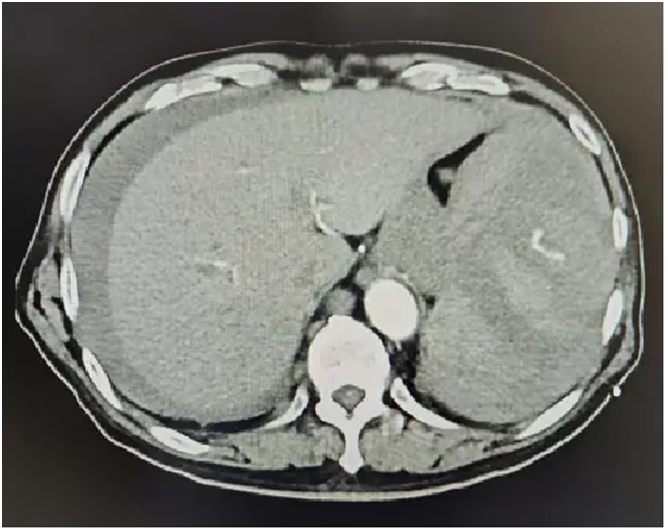

病例二:脾脏破裂,暗藏“杀机”

辛先生(化名),遭遇外伤,初步诊断为脾破裂出血。然而,在急诊介入手术过程中,医生敏锐发现破裂处竟暗藏肿瘤病灶!介入团队临危不乱,一边栓塞止血挽救生命,一边为后续肿瘤治疗提供了关键的影像学依据和干预时机。